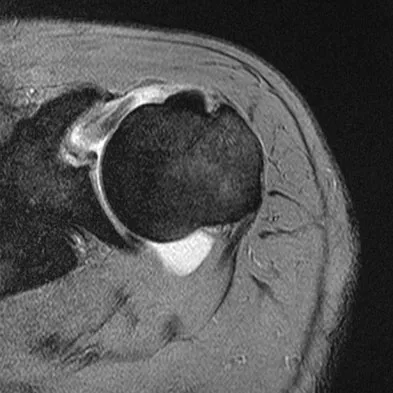

A 39-year-old man has anterior shoulder pain after landing on his abducted left shoulder while playing softball. Examination reveals a stable glenohumeral joint, pain on passive external rotation of greater than 25 degrees, and pain and weakness on belly press (Napoleon's) test. An MRI scan is shown in Figure 32. To provide maximum pain relief and return of function, management should include

Explanation